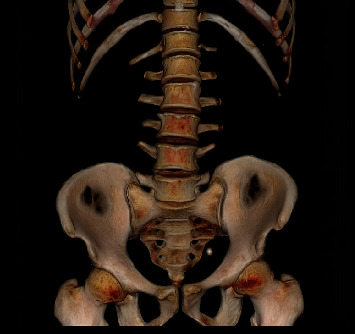

Crossed-fused renal ectopia (CFRE) is a rare congenital anomaly where both kidneys are fused on the same side. We report a case of a 52-year-old male patient who presented with central abdominal pain associated with hematuria and dysuria, with a history of left open ureterolithotomy. Abdominal computed tomography (CT) showed an 18-mm left distal ureteric stone and a CFRE with a bilateral duplex-collecting system. Left ureteroscopy and laser lithotripsy with magnetic double-J stent insertion were carried out successfully, and the patient was discharged on the same day in fair general condition.

Abstract Image